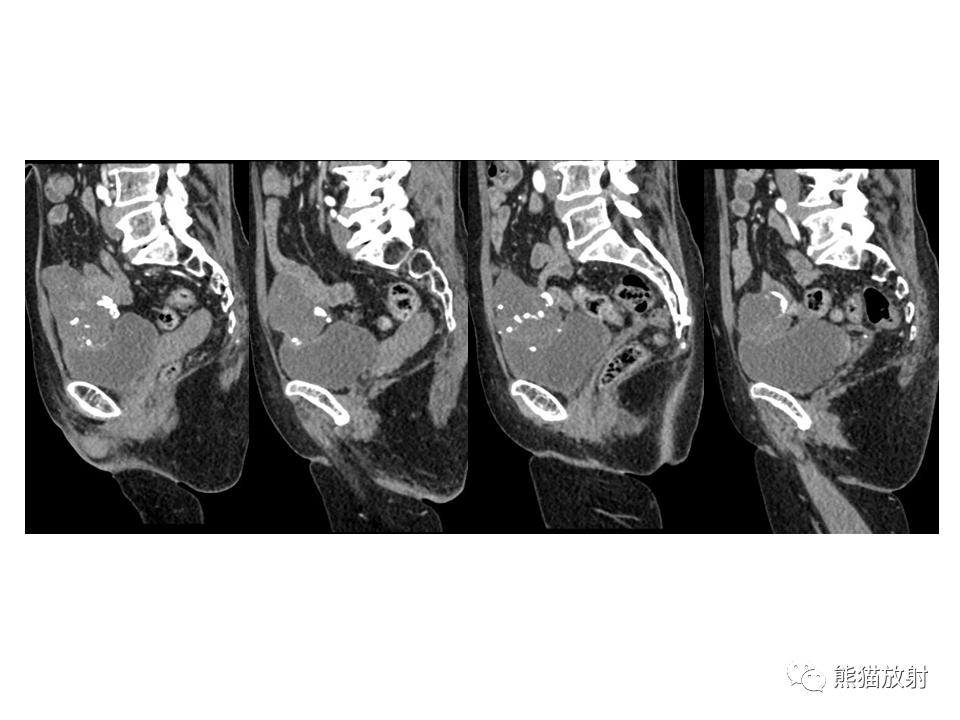

脐尿管病变影像诊断

脐尿管异常的影像表现与临床